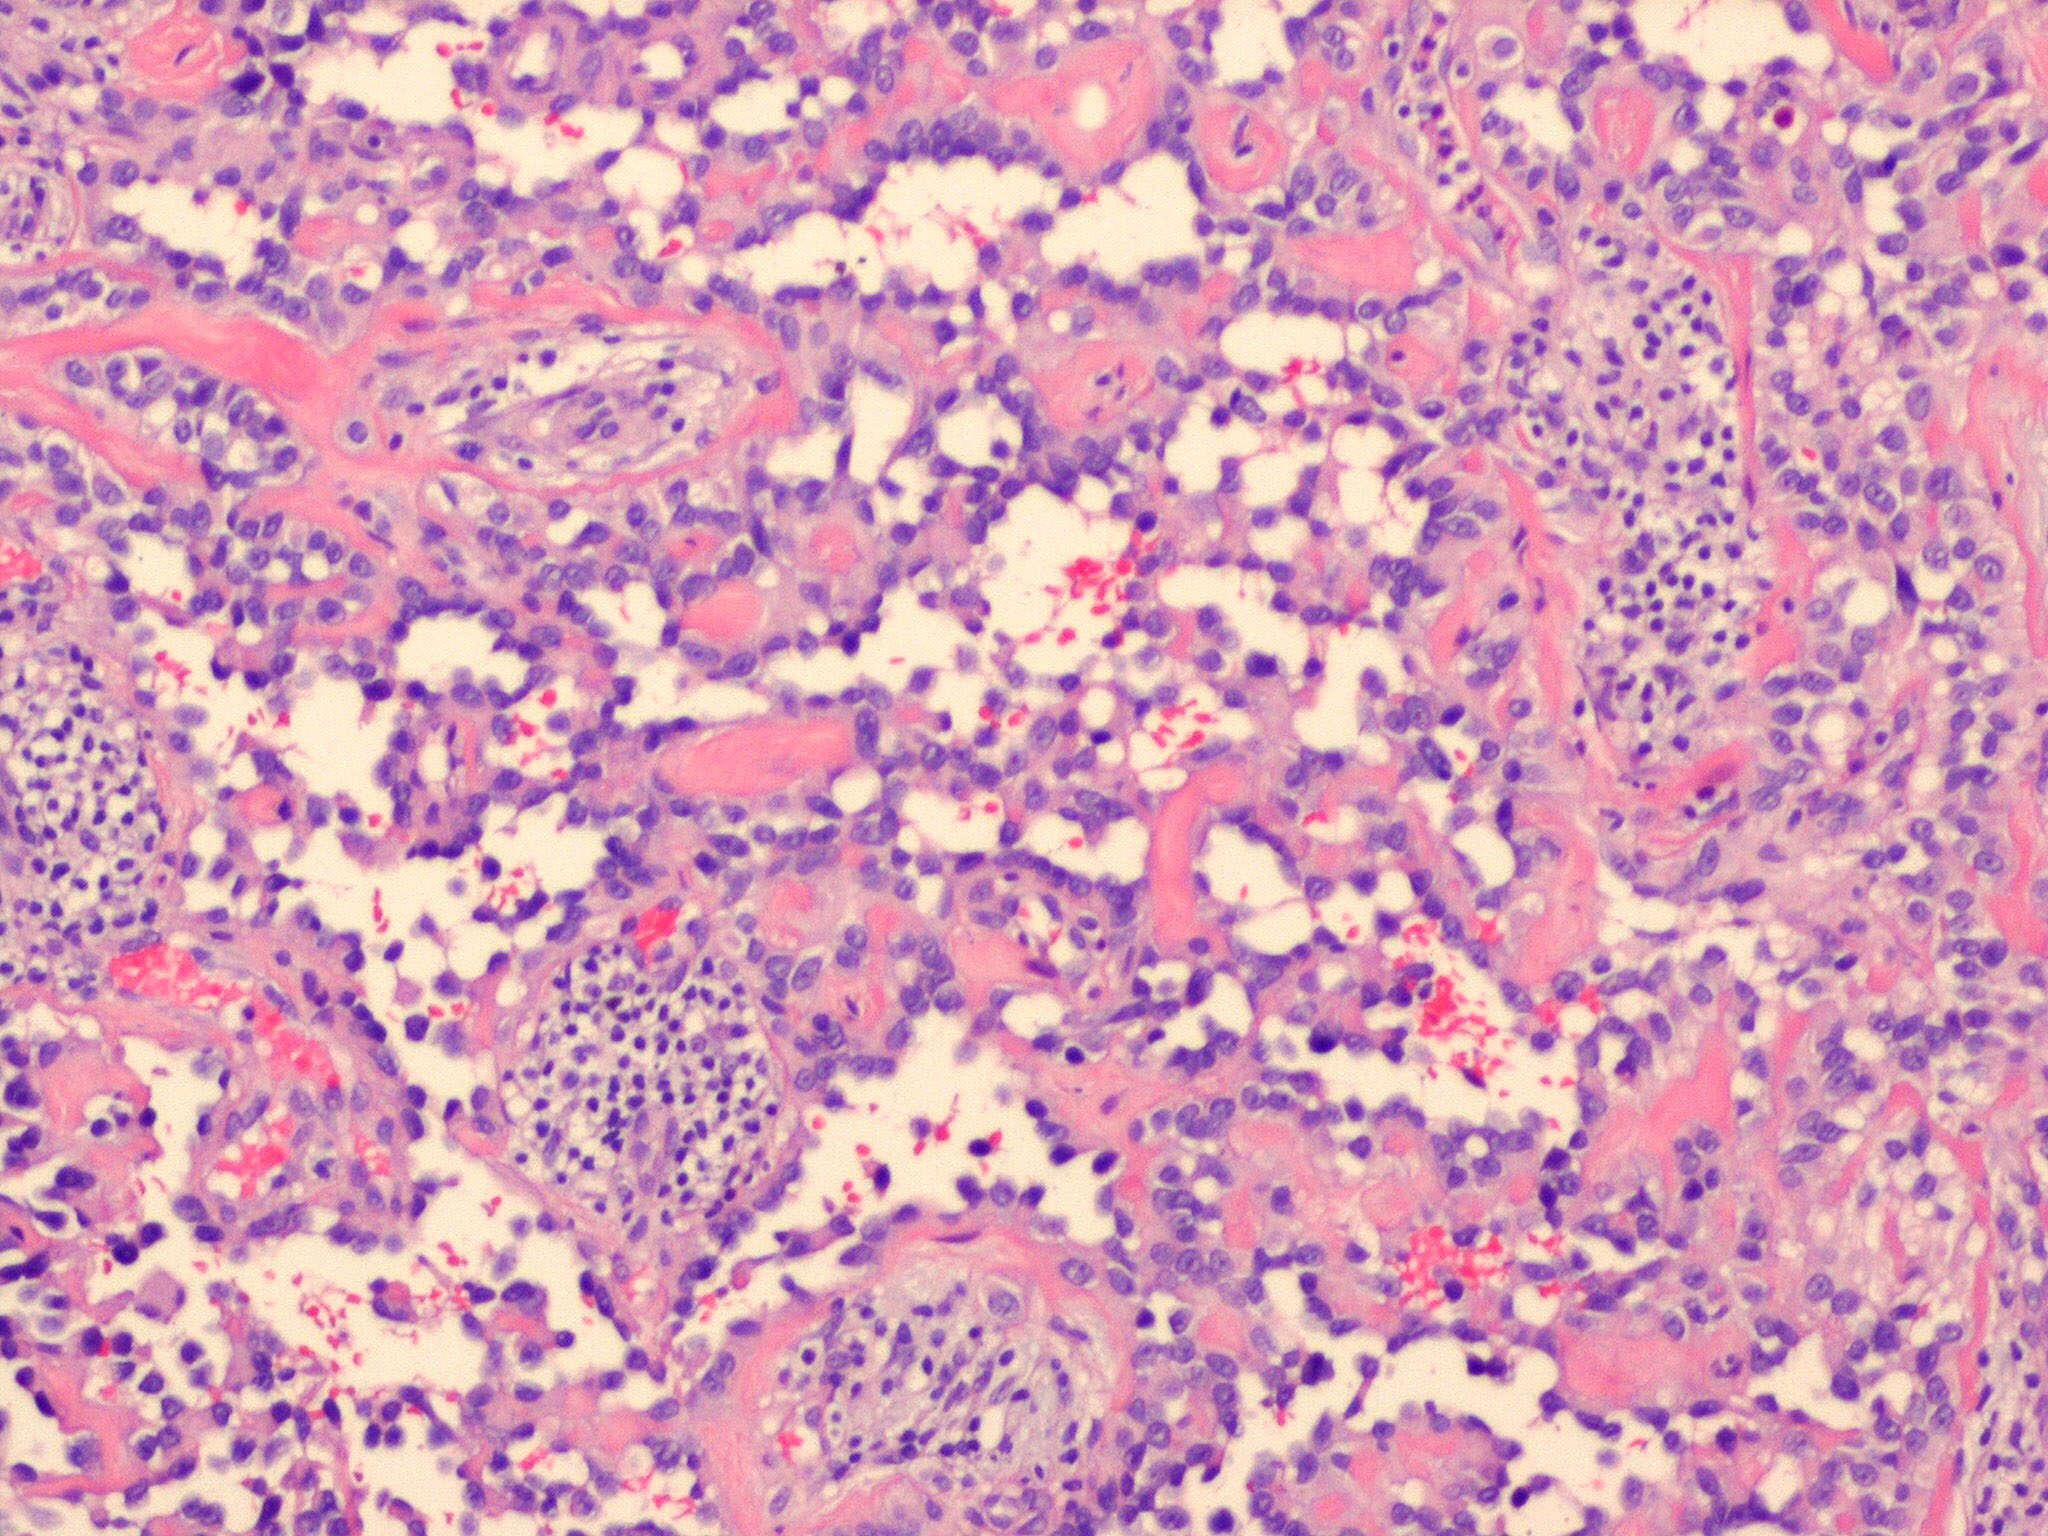

Angiosarcoma = الساركوم الوعائي